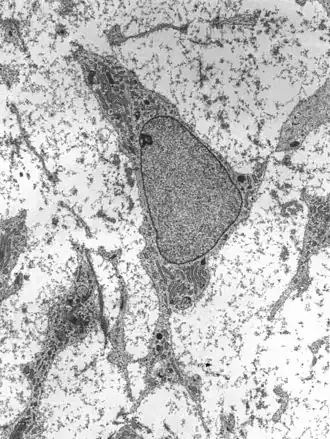

Mesenchymal stem cells within mesenchyme or the medullary cavity of a bone fracture initiate the process of intramembranous ossification. A mesenchymal stem cell, or MSC, is an unspecialized cell that can develop into an osteoblast. Before it begins to develop, the morphological characteristics of a MSC are: A small cell body with a few cell processes that are long and thin; a large, round nucleus with a prominent nucleolus that is surrounded by finely dispersed chromatin particles, giving the nucleus a clear appearance; and a small amount of Golgi apparatus, rough endoplasmic reticulum, mitochondria, and polyribosomes. Furthermore, the mesenchymal stem cells are widely dispersed within an extracellular matrix that is devoid of every type of collagen, except for a few reticular fibrils.[1]